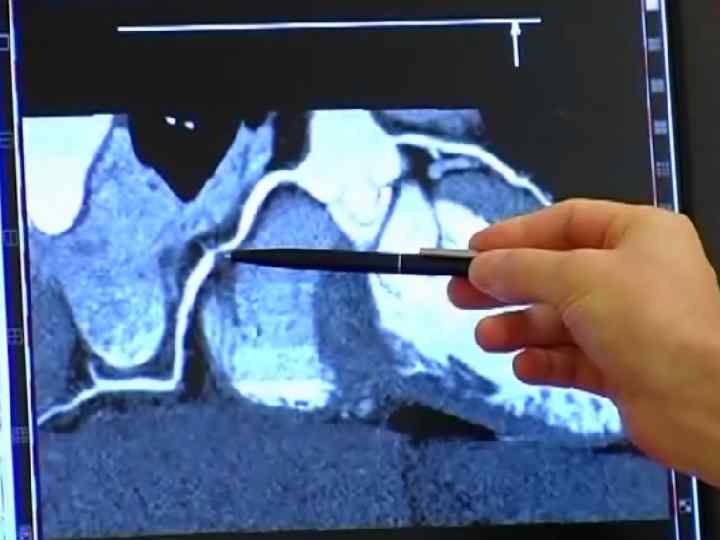

МАГНИТНО-РЕЗОНАНСНАЯ ТОМОГРАФИЯ(МРТ) СЕРДЦА Магниттi - резонанстық томография орталық жүйке жүйесi, омыртқаның ауруларын диагностика арқылы зерттеудiң аналог болмайтын сирек кездесетiн iс жүзiнде бұлшық еттiк болып табылады - буын жүйе және iшкi органдардың қатары. Сутектiң протондарын адамның организмінде резонанста негiзделгеннiң зерттеу онының магниттi алаңына үй-жайда. Сәулелiк жүктеменiң жоқтығы емделушi үшiн магниттi - резонанстық томография қауiпсiз iстейдi және бiрнеше тексерулер қатар өткiзуге мүмкiндiк бередi

Жағдайларды қатарда көк тамырiшiлiк қарама-қарсы күшейтуi бар зерттеудiң өткiзу МРТ диагностикалық қажеттiлiгi пайда болады. Зерттеудiң мәлiметтерi дәрiгер МРТ емдеушi дәрiгер немесе бағыт бойымен тек қана жүргiзiледi. Қарама-қарсы препараттың енгiзуi қосымша реакциялардың ең төменгi тәуекелiнде болады. Сiзгеге контрасты заттың енгiзуi жағдайда сауалнаманы толтыруға ұсыныс жасайды - қарама-қарсы препараттың көктамырiшiлiк енгiзуiне ақпараттық келiсiмнiң парағы.

Зерттеуге абсолюттiк қарсы көрсетулермен жатады: ми ыдыстарында кардиостимулятордың бар болуы, ферромагниттi имплантовтары, клипс. Зерттеу бұл жағдайдалардағы қатал қарсы көрсеткен. (зерттеу өткiр қажеттiлiктiң жанында жүргiзiле алады) салыстырмалы қарсы көрсетулерге металлдың мазмұнымен жүктiлiктiң бiрiншi триместрi, жүректiң жасанды клапандары, орнын толтырмалған жүрек мүкiсi, инсулин сорғылары, импланты, металлдық брекетыларда әкетедi. Сонымен бiрге темiрi бар бояуларды қолданумен салыстырмалы қарсы көрсетулер сияқты қарау керек болуға iстеп шығылған татуировкалар.